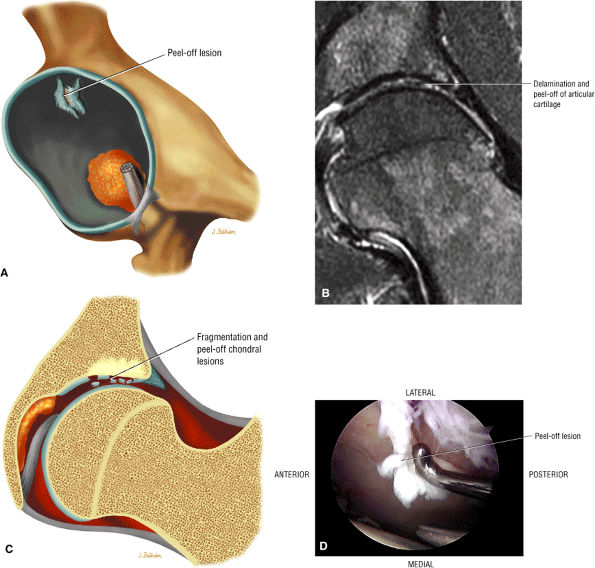

-

A decreased femoral head-neck offset

A dysplastic femoral bump at or adjacent to the lateral physeal scar femoral head-neck junction (Fig. 3.185)

A bump-osteophyte complex (Fig. 3.186) where the dysplastic femoral bump is anterior to the lateral to posterolateral osteophyte as visualized on coronal MR images, and the osteophyte may demonstrate hyperintense edema on FS PD FSE sequences